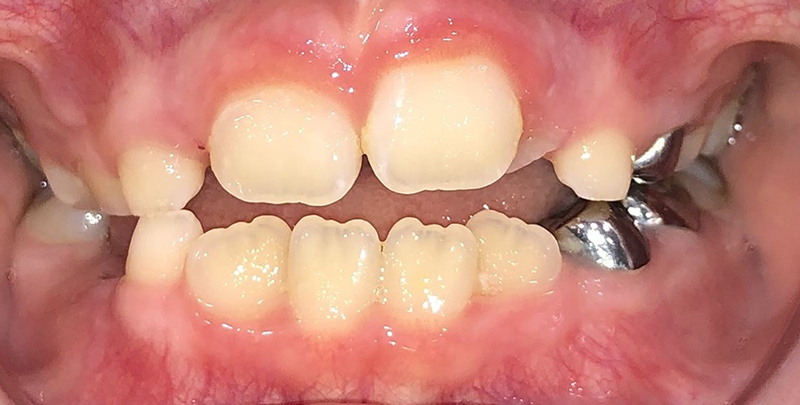

Actual Patient: Bailey

Before

Severe “Overbite”, BUCK TEETH, Narrow Jaws, Severe Deep Bite

Right & Left Sides